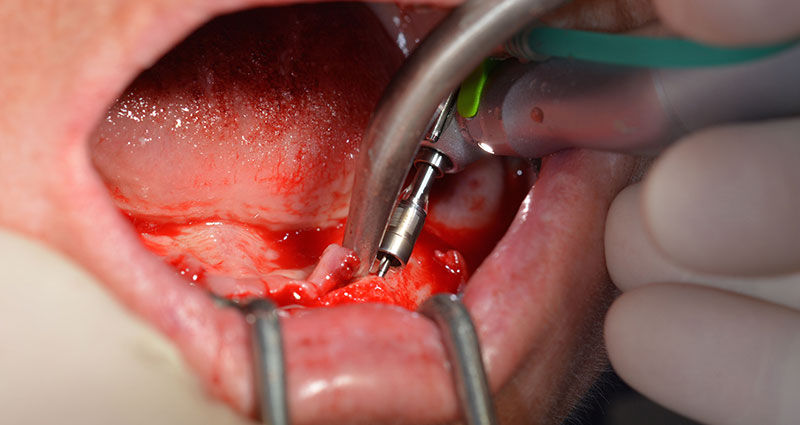

Die 64-jährige Patientin wurde mit einer Unterkiefer-Restbezahnung 38, 33 und 43 und einer klammerbefestigten Interimsprothese im Unterkiefer vorstellig (Abb. 1 und 2).

Nach der Entfernung der Unterkiefer-Restbezahnung erfolgte die krestale Schnittführung von Regio 37 bis Regio 47.

Zunächst wurde das Foramen mentale als limitierende anatomische Struktur dargestellt und die krestale Kortikalis mit dem geraden Handstück und einem großen Rosenbohrer geglättet (Abb. 4).